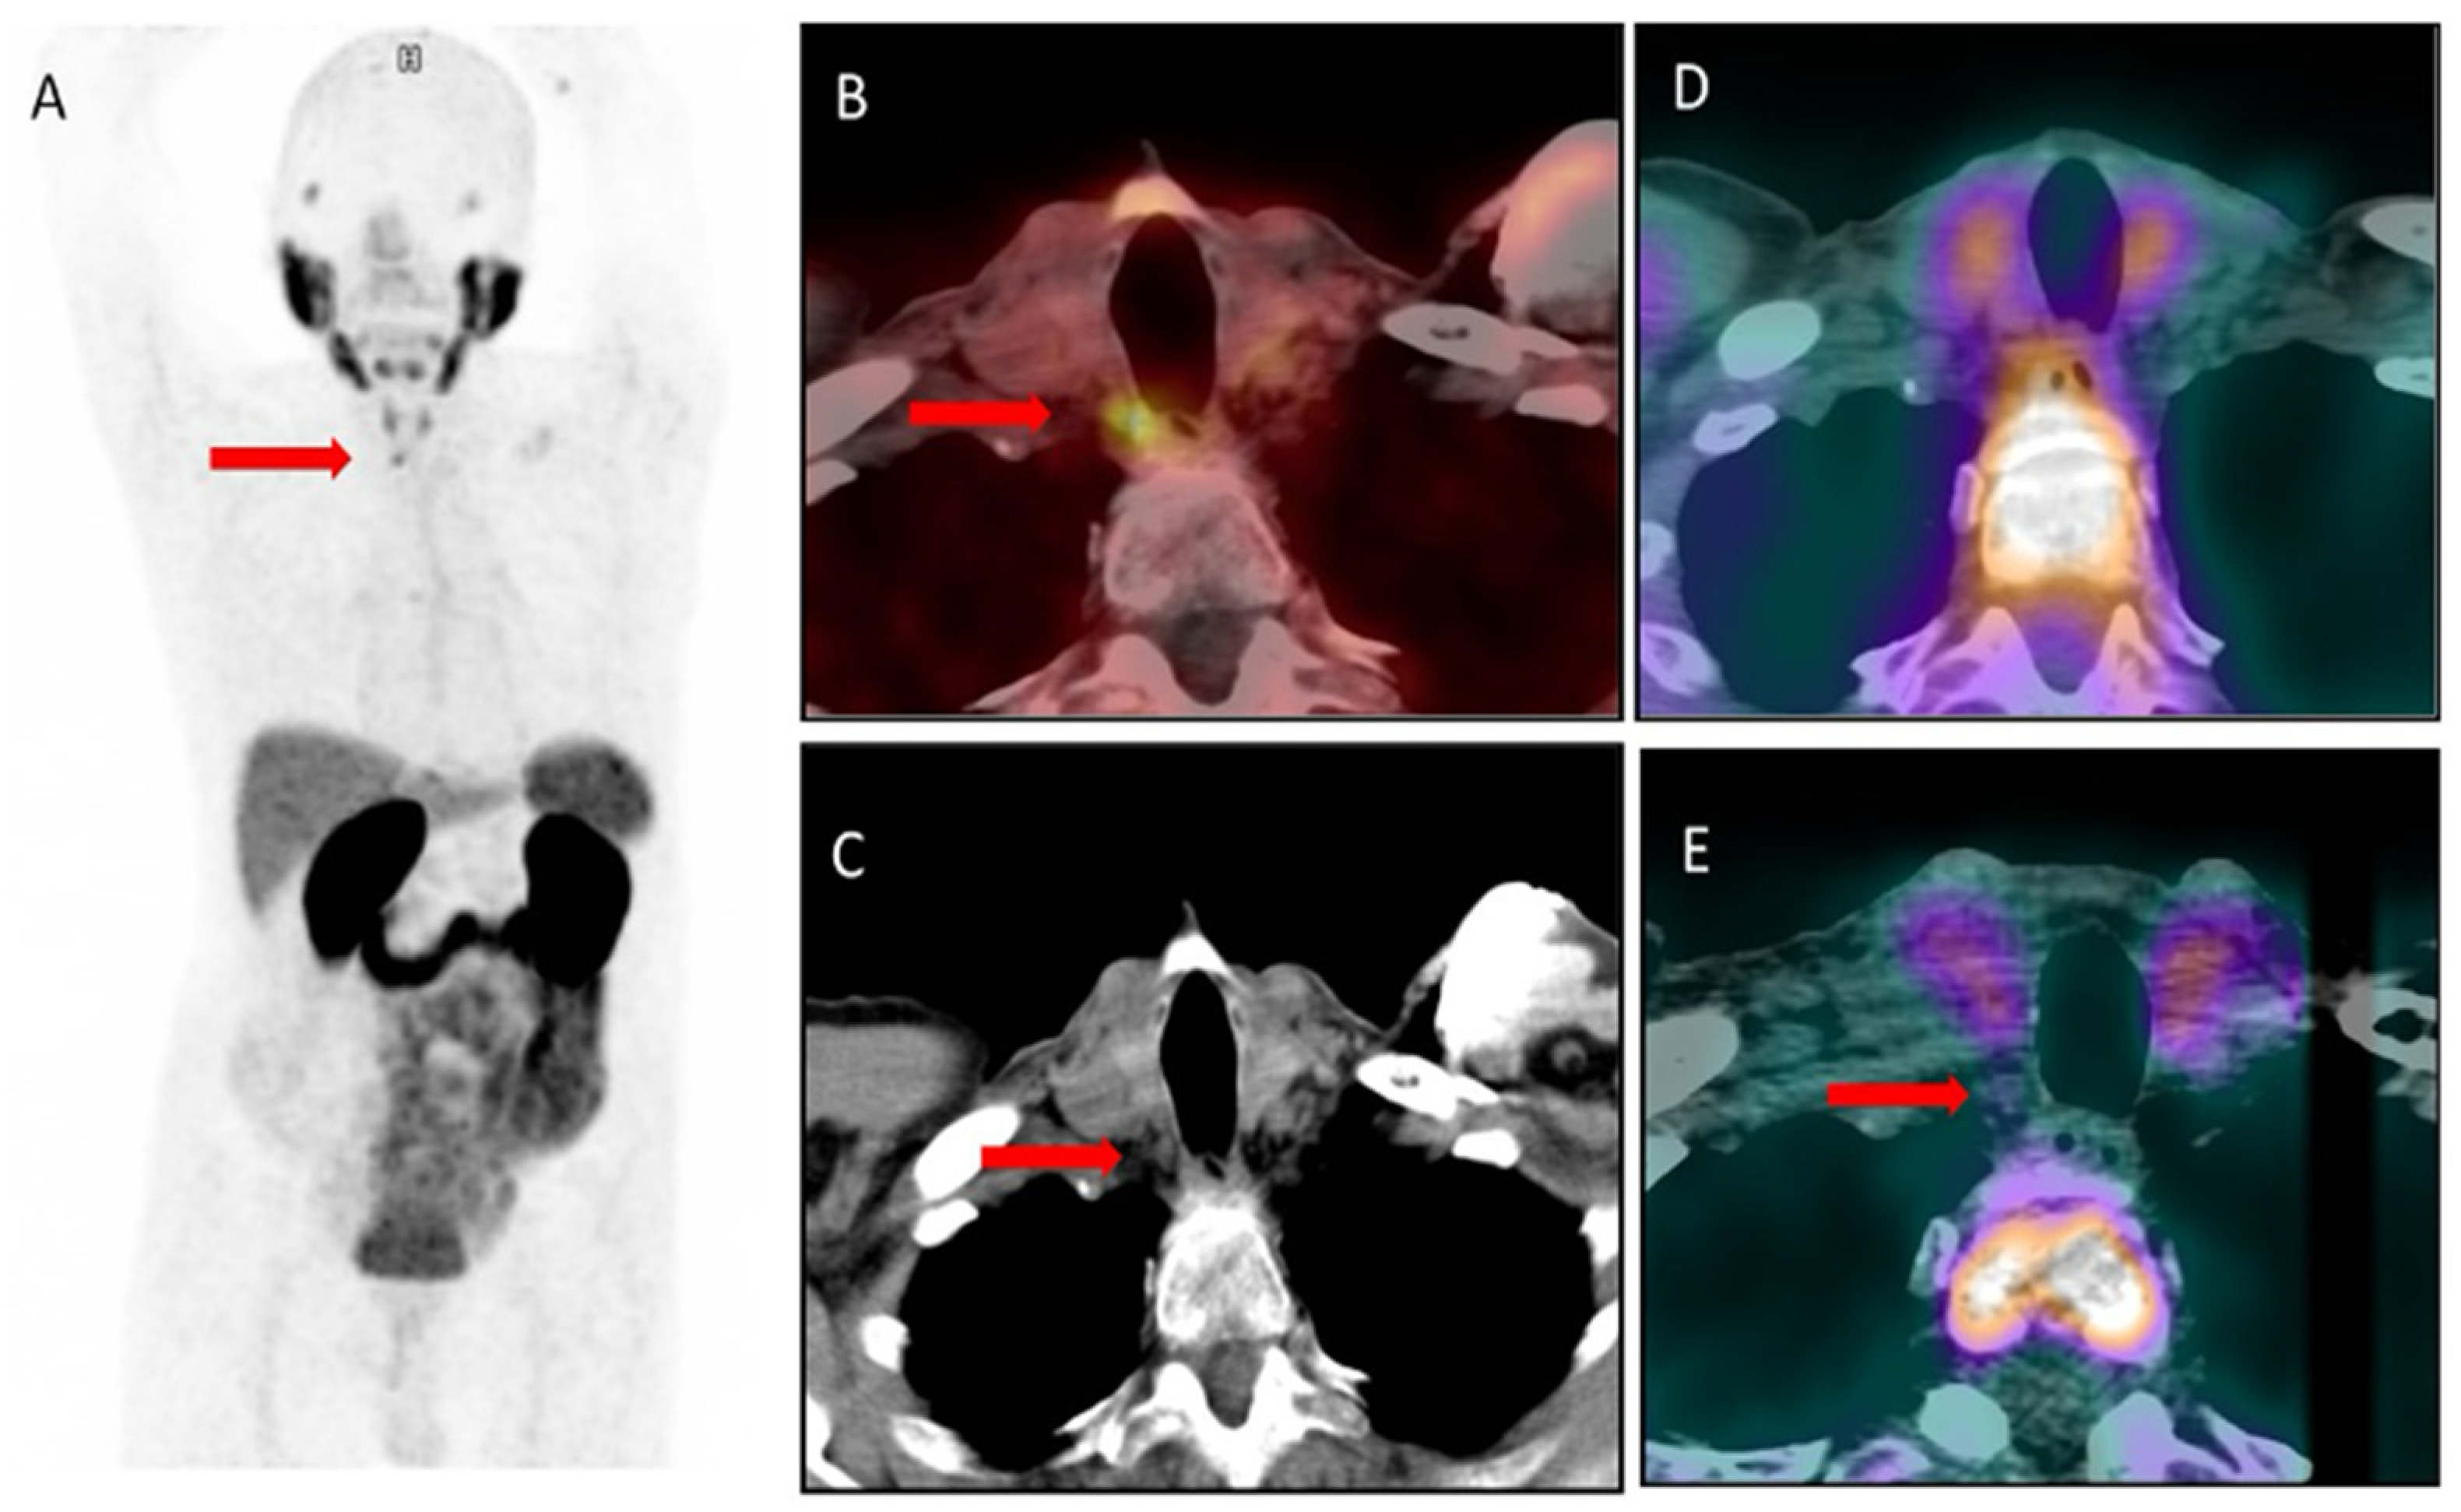

2. Results—Case Presentation